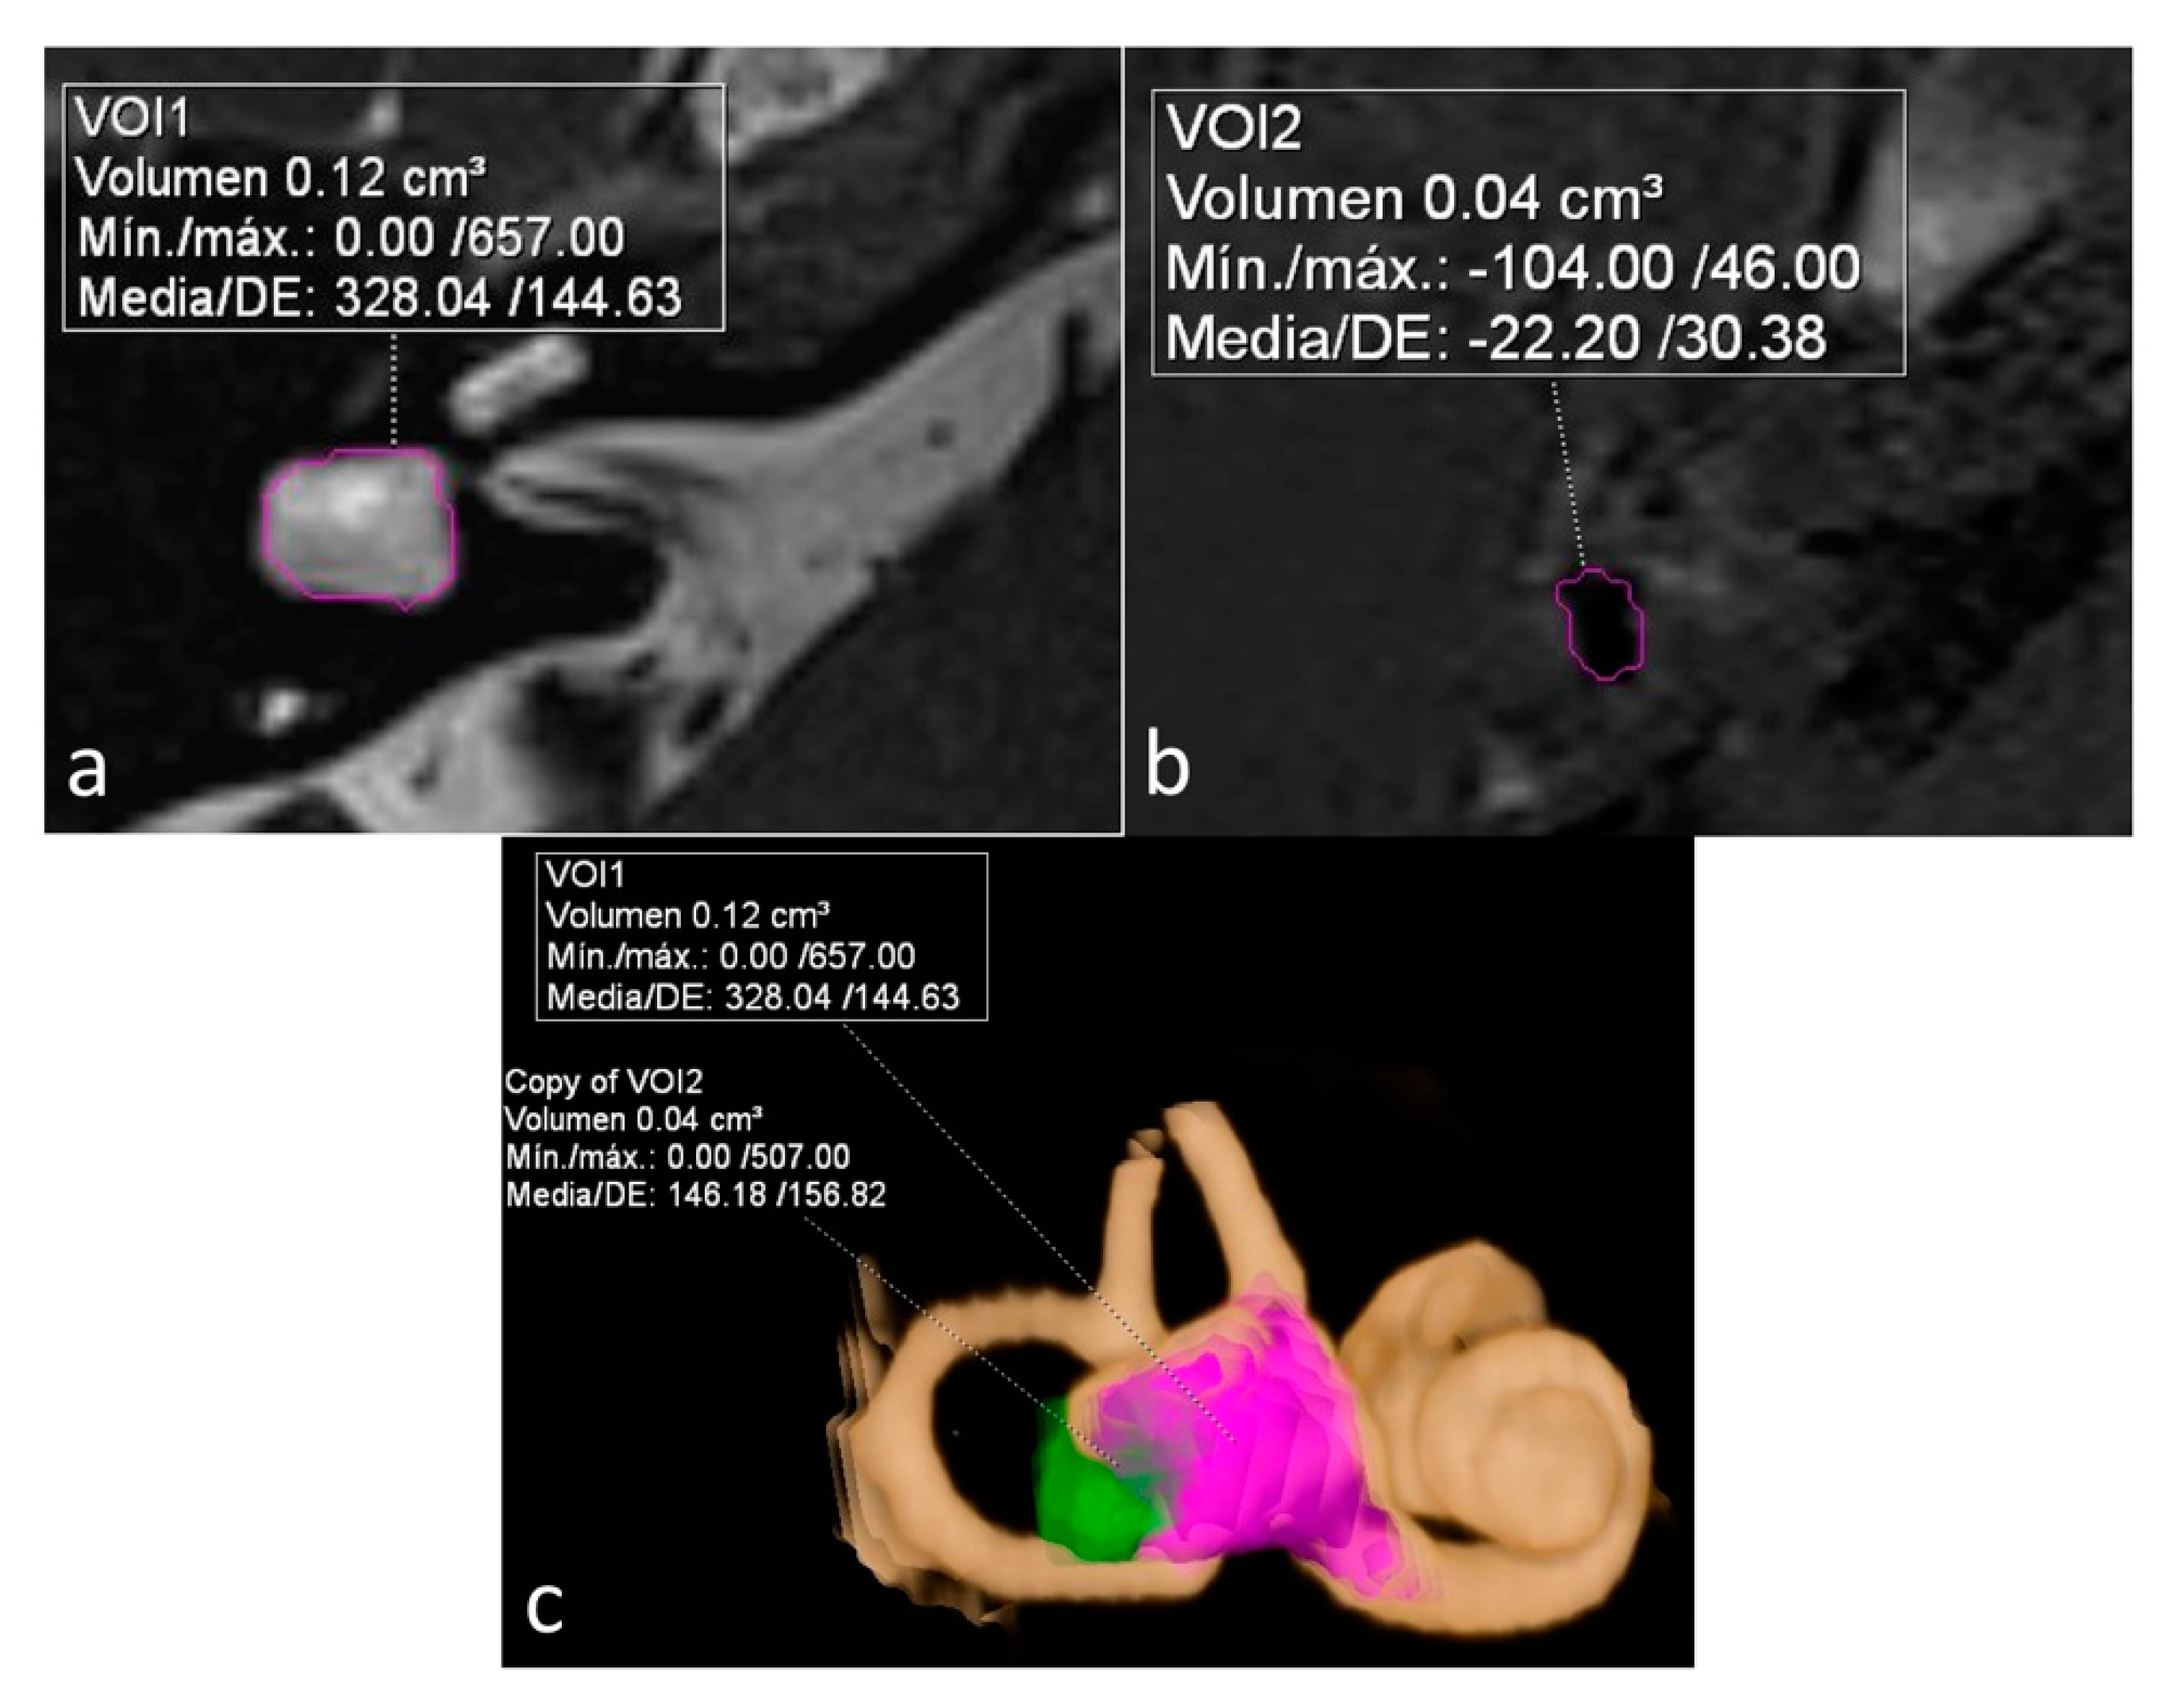

On a dedicated workstation with Syngo.via software (Siemens Healthineers, Erlangen, Germany, Client version 5.1), we used the MR cisternography sequence (T2 3D SPACE) to measure the total volume of vestibular lymph fluid (bright signal) on diseased ears defined as bright signal within the cystoid cavity formed by the union of the vestibule and the aplastic LSCC in a semi-automatic fashion. An experienced radiologist manually delineated the boundaries of the vestibule in all slices, and the software automatically calculated the total volume. As no central bony islands were depicted, no subtractions to this total volume were needed. The total volume of endolymph within the cystoid cavity was also calculated semi-automatically using the 3D-IR with REAL reconstruction sequence manually tracking the low signal in the vestibule. The endolymphatic volumetric ratio (ELR) [9] was calculated as the total vestibular endolymphatic volume divided by the total vestibular cavity volume multiplied by 100. The radiologist was not aware of the clinical information during the process of volume segmentation (Figure 1).

Figure 1.

Sequences used for the calculation and depiction of endolymphatic and total vestibular volumes and endolymphatic ratio (ELR). (a) Heavily T2 weighed cisternography sequence depicts lymph within a right cystoid lateral semicircular canal (LSCC). A semi-automatic calculation of total vestibular lymph volume is shown. (b) 3D-IR-REAL hydrops sequence depicts low signal (dark) vestibular endolymphatic volume. (c) 3D volume-rendered image of the inner ear based on the cisternography sequence with color coded overlay of both vestibular and endolymphatic hydrops volumes.

The other two patients, both with unilateral LSCCD, showed intermediate percentages. One patient was suffering from hearing loss without vestibular symptoms (patient 3) and showed an ELR of 33% (shown on Figure 1). The other patient had symptoms of probable MD (patient 6) and showed an ELR of 42% (not shown).